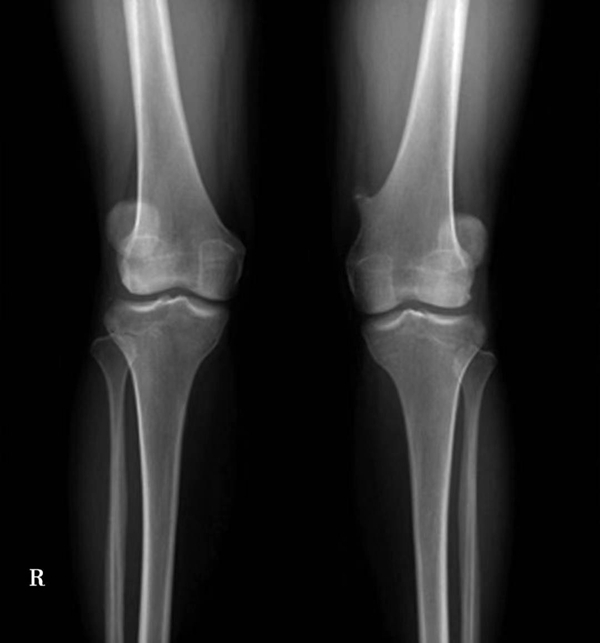

正常髌骨中心点应位于下肢轴线上或稍内侧(图1)。对于髌骨不稳定,膝关节正位像可见髌骨偏离正常的位置,向外侧移位(图2、图3)。

图3 膝关节正位X线成像显示了右膝髌骨偏离正常的解剖位置,明显向外侧移位